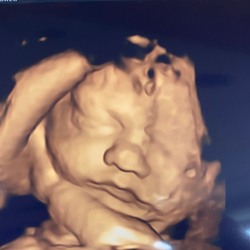

Ik voeg me graag bij deze groep. Afgelopen vrijdag is onze dochter geboren met precies 34 weken, na een keizersnede vanwege placenta-insufficiëntie. Gelukkig hebben de longrijpingsinjecties goed hun werk gedaan en heeft ze een mooie start kunnen maken.

Behalve dat ze prematuur is, is ze ook dysmatuur. We zijn intens dankbaar en gelukkig dat ze er is — klein, maar krachtig. Tegelijkertijd is het ook een pittige en onzekere tijd. Ik weet nog niet hoe de komende weken eruit zullen zien, maar samen met haar papa en grote broer gaan we er alles aan doen om er het beste van te maken.

Ik sluit me graag aan! 2 mei is ons dochtertje geboren met 35+5. Ze woog 1604 gram en was 41,5cm (Dysmatuur en Prematuur)

ik sluit me ook aan bij deze groep😊 op 25 april 2024 ben ik bevallen van onze prachtige dochter op een termijn van 29 weken precies doormiddel van een acuut hellp syndroom en eclampsie. ze was 35 cm lang en woog 1175 gram! Ze is geboren in Hongarije en hebben een hele reis achter de rug gehad.